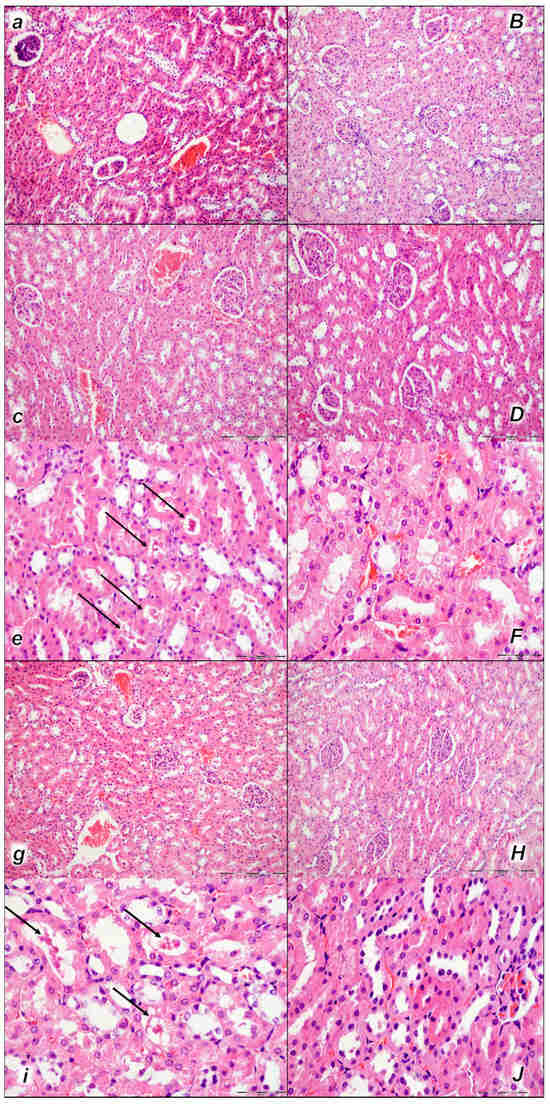

Figure 9.

Kidney, microscopy presentation (a–F). After laurate application into the inferior caval vein control rats (small italic letters), moderate vascular congestion was shown in renal parenchyma, interstitial edema at 15 min (a), and moderate vascular congestion, and interstitial edema, and intratubular hyaline casts (black arrows) at 30 min (c,e) and at 60 min (g,i). No changes in BPC 157-treated rats (capital italic letters) were observed at 15 min (B), 30 min (D,F), and 60 min (H,J) after laurate application into the inferior caval vein. (HE staining; magnification 200×; scale bar 200 μm (a,B,c,D,g,H); magnification 600×; scale bar 50 μm (e,F,i,J)).